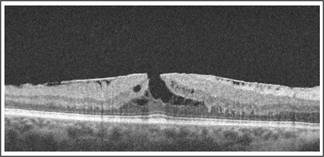

Fig. 1: Vitreomacular traction.

Of the 83 patients labeled UVL, OCT detected an organic cause to the visual loss in 37. The male: female was 17:20. The mean age in years was 50.10 ± 17.11yrs. The minimum age was 04yrs and maximum age was 80yrs. The various pathologies detected on OCT, along with the demographic data are presented in Table 1 and shown in Figures 1-10. 46 patients of UVL had normal OCT scans.

Fig. 2: Stage 1b macular hole. Dehiscence of the neurosensory retina.

Vitreomacular traction syndrome was amongst the most common causes detected on OCT that could explain UVL. SD OCT enables us to study the posterior vitreous and the intricate relationship it has with the inner retina. We are easily able to differentiate vitreomacular adhesion from vitreoschisis and vitreomacular traction which is not clinically visible. Also the 3-D image reconstruction feature can help identify surgical plans improve pre operative planning and therefore optimize surgical outcomes. Koizumi et al9 performed three dimensional scanning of VMTS and demonstrated that VMTS is frequently associated with undiagnosed epiretinal membranes that can negatively impact vision and the surgical ease with which vitreous traction can be relieved per operatively. We also observe ERM in 4 of our cases of VMTS.

Macular holes are a consequence of centrifugal displacement of cone receptors to form a dehiscence at the umbo. Abnormal vitreofoveolar interaction is said to lead to this pathology. Clinically early macular holes Stage 1 and full thickness macular holes less than 200 microns are difficult to detect.

Early macular holes may be seen on OCT as a schitic cavity at the level of the outer plexiform layer and the outer nuclear layer10. This then extends to involve the IS/OS junction and the layer representing the interaction of the cone outer segments with the RPE.11